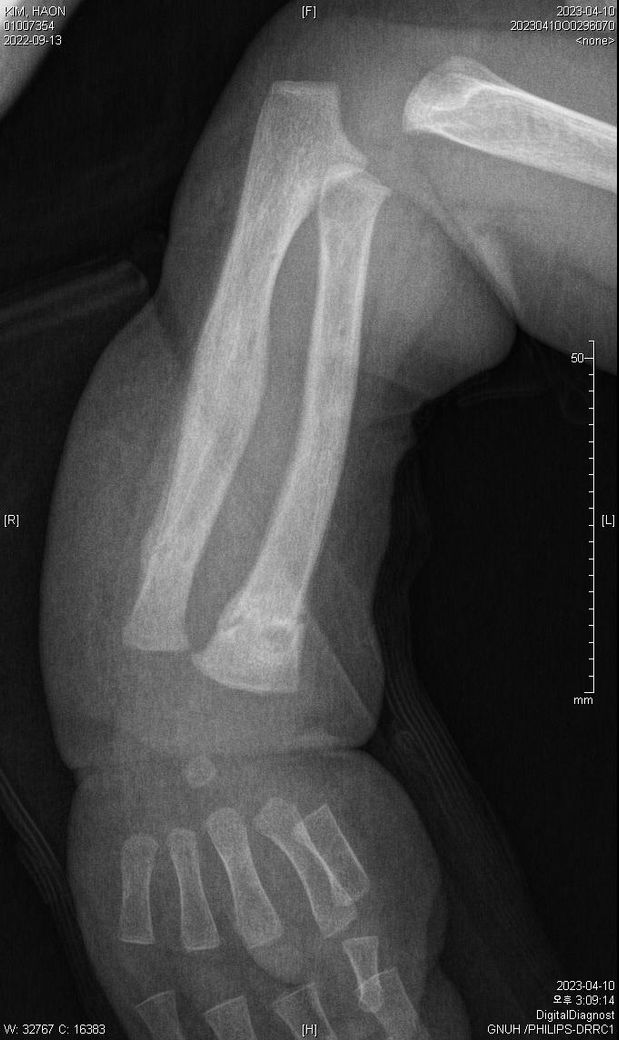

어떤 의사분 발언에 의하면 첨부된 4월 10일 x-ray사진처럼 유합직전의 다량의 칼러스가 발생되었다고 합니다.

아래에 3월 30일 x-ray 사진 2개, 4월 10일 X-ray 사진 2개 씩 첨부드립니다.

첨부된 사진에 X-raY 촬영 날짜가 기재되어 있습니다.

Dating fractures in infants, Clinical Radiology., Volume 66, Issue 11, November 2011, Pages 1049-1054 문헌을 보면 뚜렷한 가골 (callus)은 수상 20일쯤 확인되는걸 알 수 있습니다. 올려주신 사진을 보면 04.10에는 뚜렷한 가골이 관찰되기 때문에 20일 전인 03.20 이전일 거라고 예상이 됩니다. 03.30 X-ray에는 가골이 전혀 확인되지 않기 때문에 03.10 이후일 가능성이 높아보이고 03.10~03.20 사이가 가장 가능성이 높지 않을까 생각됩니다.